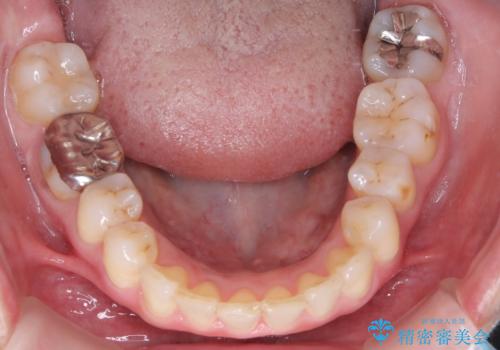

【インビザライン】前歯の凸凹を治したい

- 前歯の凸凹を主訴に来院されました。

臼歯部の遠心移動を行いながらスペースを作り、インビザラインにて前歯をきれいに並べることができました。

今回の治療計画では臼歯部の遠心移動とIPRを行っています。